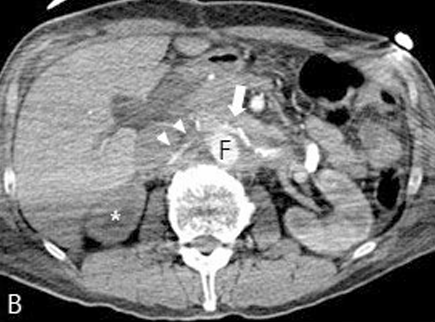

Contrast-enhanced CT coronal scan image (A) showed aortic dissection from aortic arch to infrarenal aorta and relationship of true lumen (T) and false lumen (F). Axial CT scan

Fig 1B

Axial CT scan (B) showed luminal narrowing of true lumen (white arrow) due to the compression of false lumen (F) and stenosis of bilateral renal arteries, which were more severe in right side (arrowheads). Decreased perfusion of right renal parenchyma (asterisk) was also noted.

Fig 1C

Curved multiplanar image at aortic arch level (C) demonstrated the proximal intimal tear site of the dissection (black arrow).